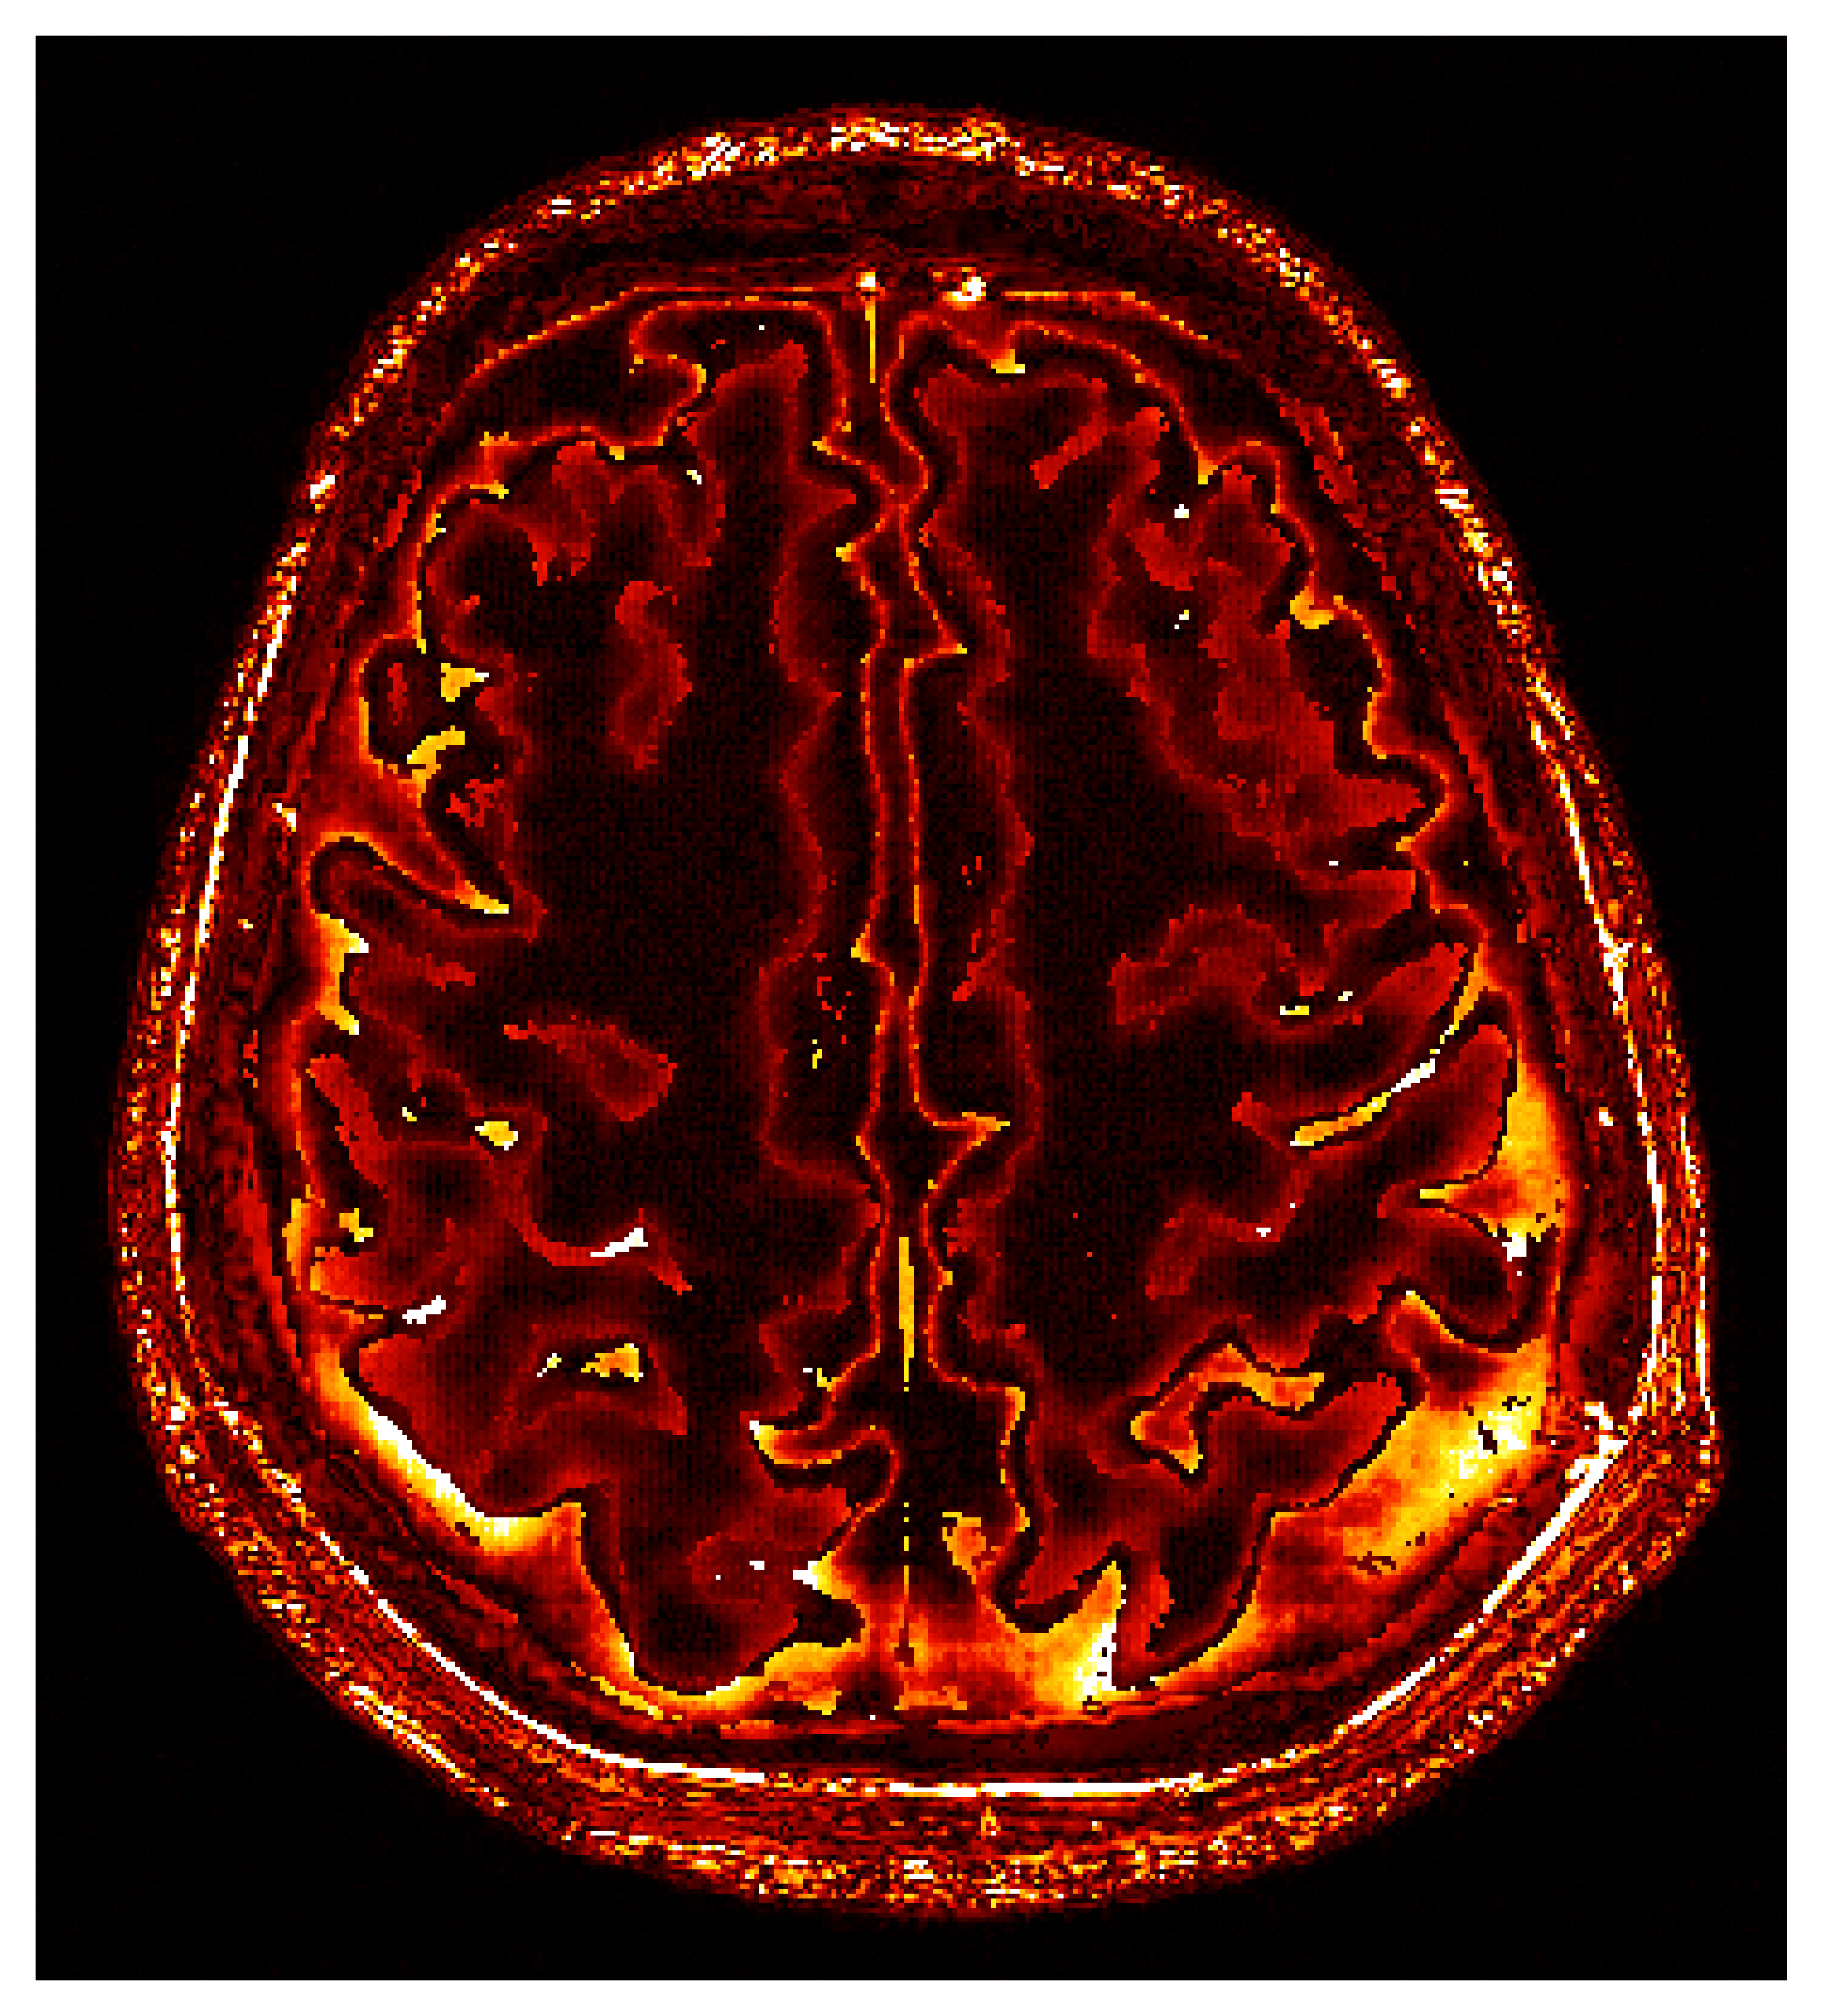

To overcome the end-to-end inference problem, we apply one iteration of ASPIRE by training a CNF on pairs, , where the ’s represent the score-based summary statistics at the fiducial points, , taken to be the uniform water velocity for all samples. An example of this initial summary statistic is shown in Figure 8. While the outer edge of the skull is reasonably well delineated, the inner edge of the skull is still poorly resolved and details inside the skull are mostly absent. However, the inference based on these initial summary statistics, shown in Figure 9, present a significant improvement over the baseline (cf. Figure 7), despite the presence of strong imaging artifacts in the summary statistics. The improvements concern the skull’s structure in particular, although details within the skull remain elusive due to the summary statistic’s limited information. To enhance fidelity further, ASPIRE 2 (shorthand for ASPIRE at iteration ) is applied by recalculating the score at the new posterior mean estimate for each training sample. Given these new training pairs, the next CNF is trained. While posterior sampling is efficient with CNFs (using Equation 4), recalculation of the score for each sample is computationally intensive, a topic we address in Section 6.6.

After the refinements of ASPIRE 2, significant improvements are evident in the posterior samples, particularly in capturing the structures within the brain tissue itself. The mean of these posterior samples, displayed in Figure 10, is clearly enhanced in resolution and details. We attribute these enhancements to the increased informativeness of the summary statistic in the second iteration compared to the information yielded by the initial iteration. A detailed inspection of the second summary statistic (shown in Figure 8) reveals more detail on the internal brain structures. Unlike the first summary statistic (cf. Figure 8), which primarily delineated the skull, the second iteration’s summary statistic better ‘illuminates’ the softer tissues within the brain, offering a more informative image for the posterior network. Thanks to accounting for the scattering at the skull, the acoustic illumination of the brain is improved significantly. Accurately resolving the skull structure is an important consideration as noted by [65].